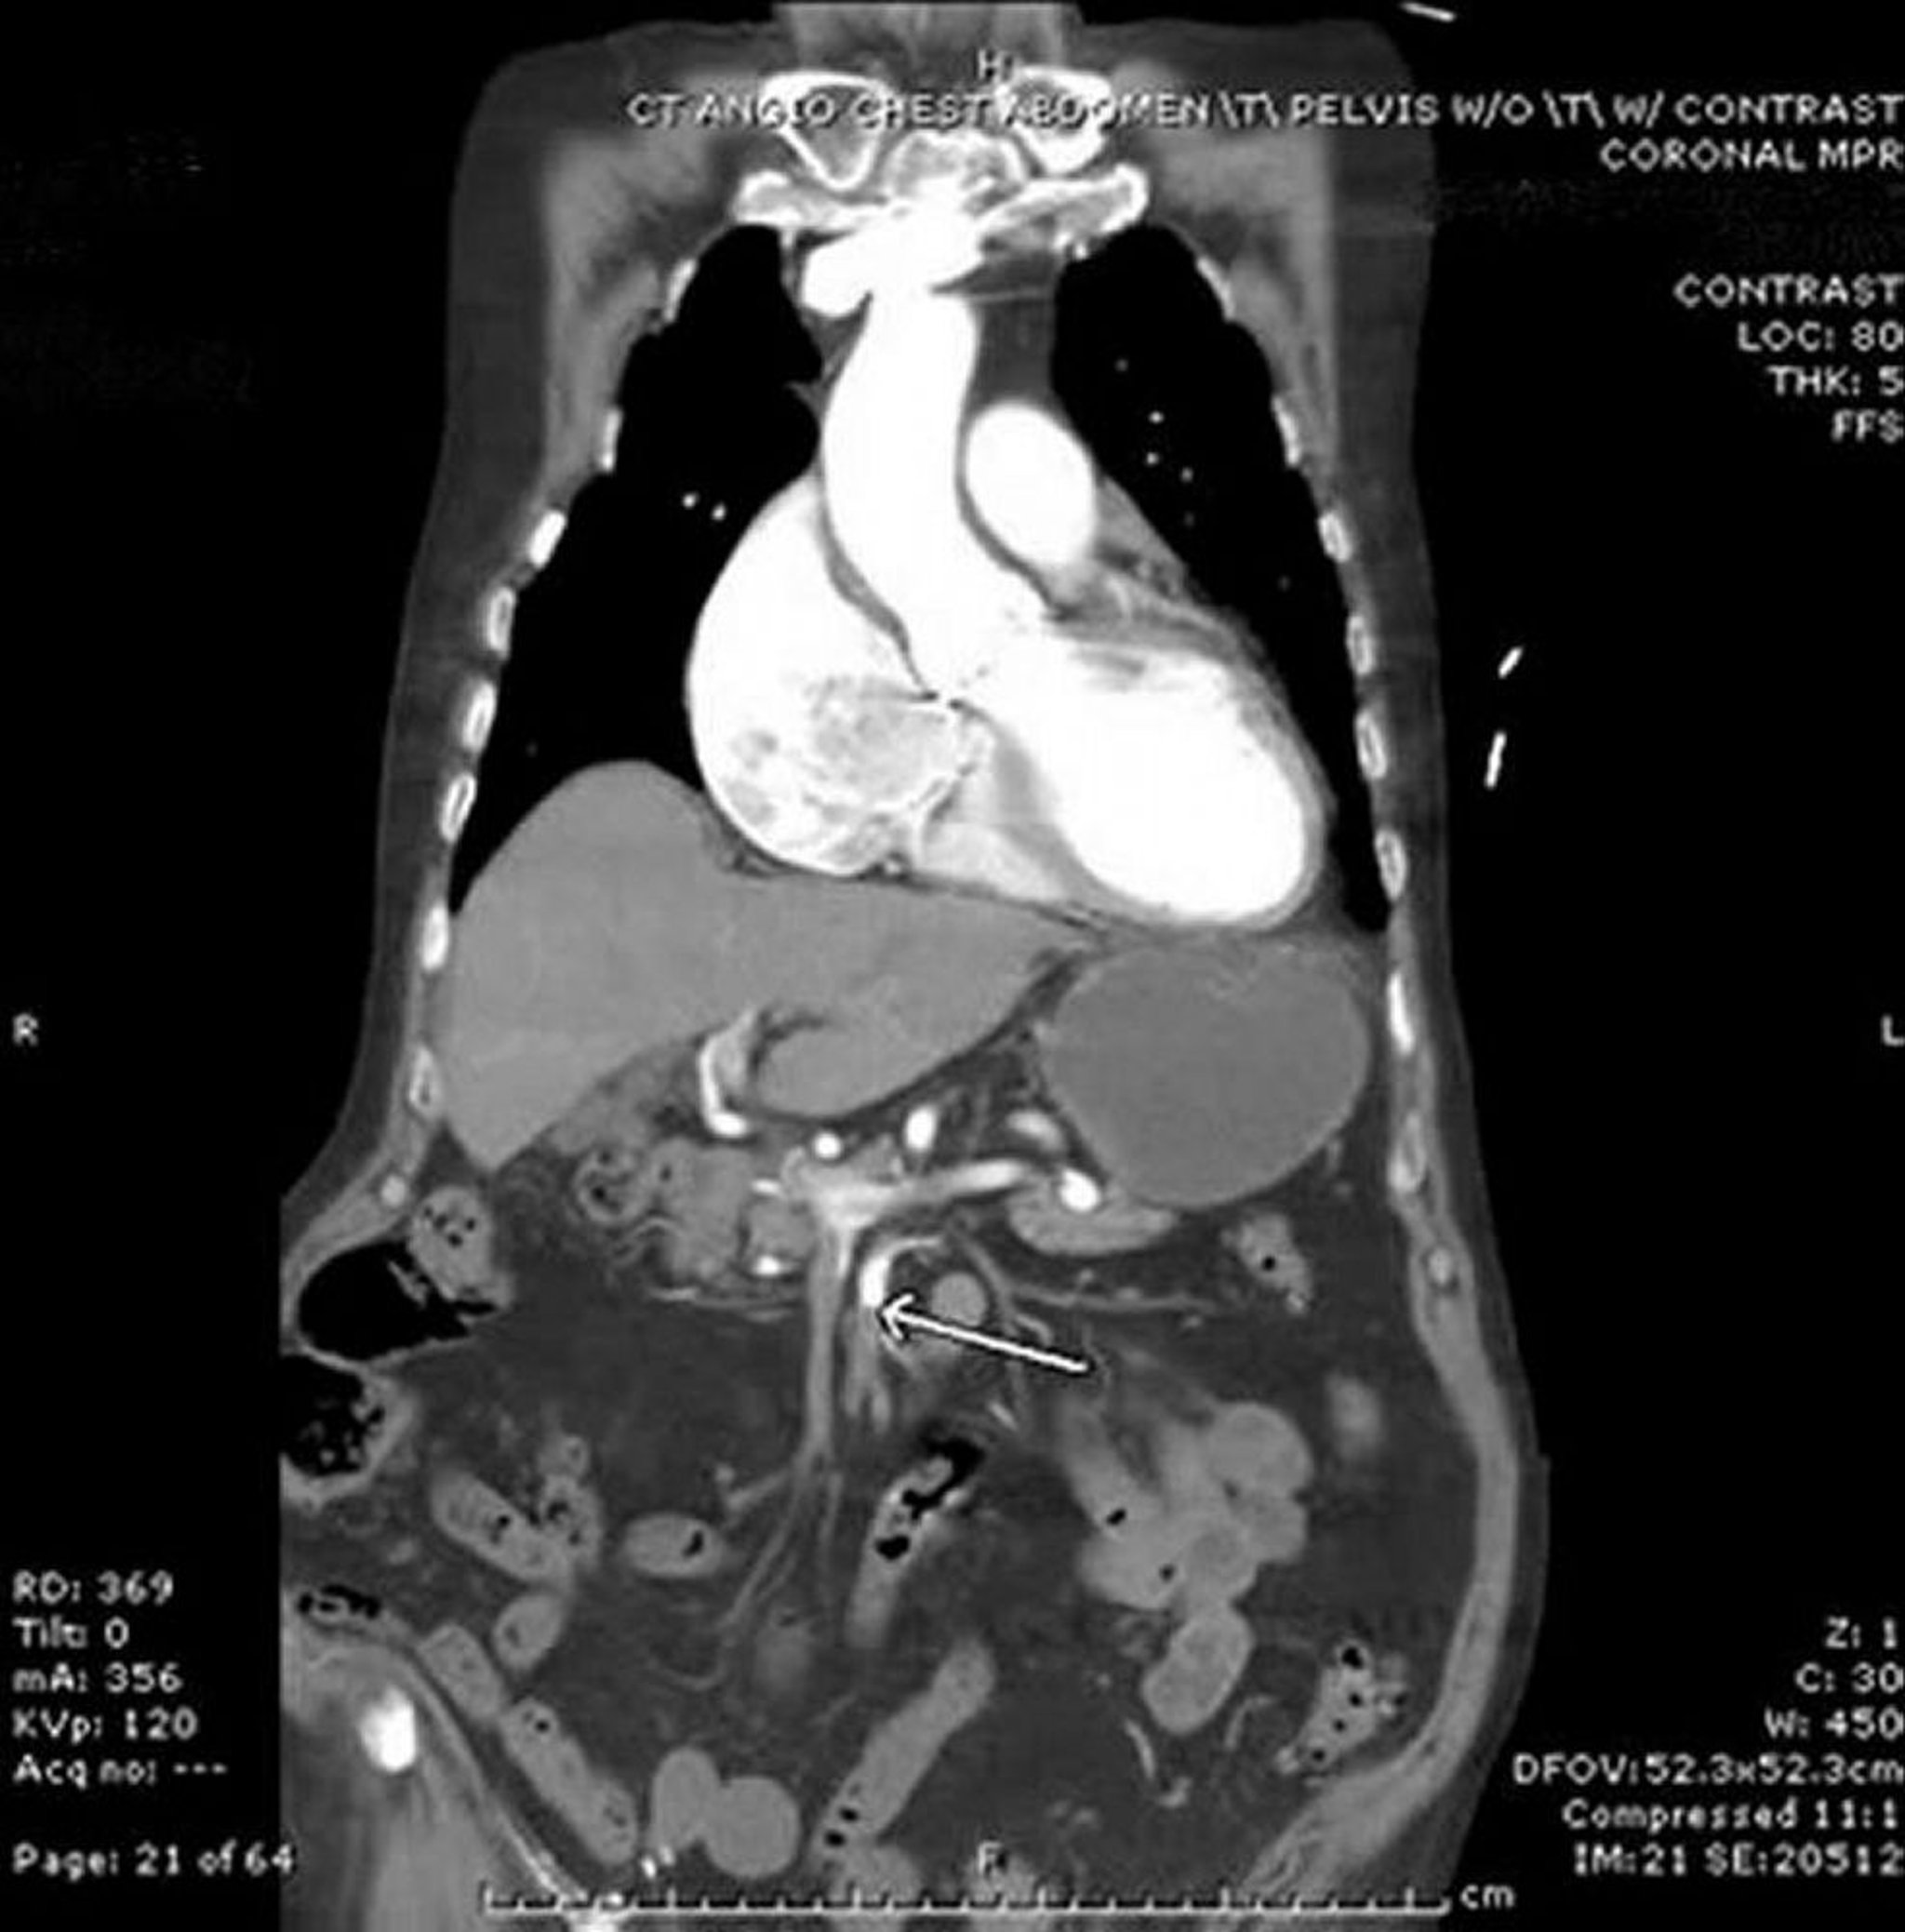

Mesenteric Ischemia (CT Angiogram)

In this image, the arrow points to the superior mesenteric artery, which has an abrupt cutoff of IV contrast. Some thickening of the small bowel in the left abdomen is seen. This case of embolism is from the heart in a patient with atrial fibrillation.

Image provided by Parswa Ansari, MD.